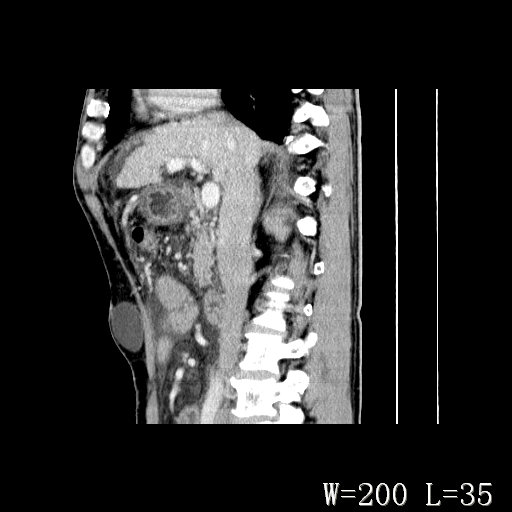

男,52岁,门脉高压断流术后1年,发现腹部肿物2月。

1)前腹壁中线区(脐上方)囊性占位性病变,考虑淋巴囊肿。2)腹水。